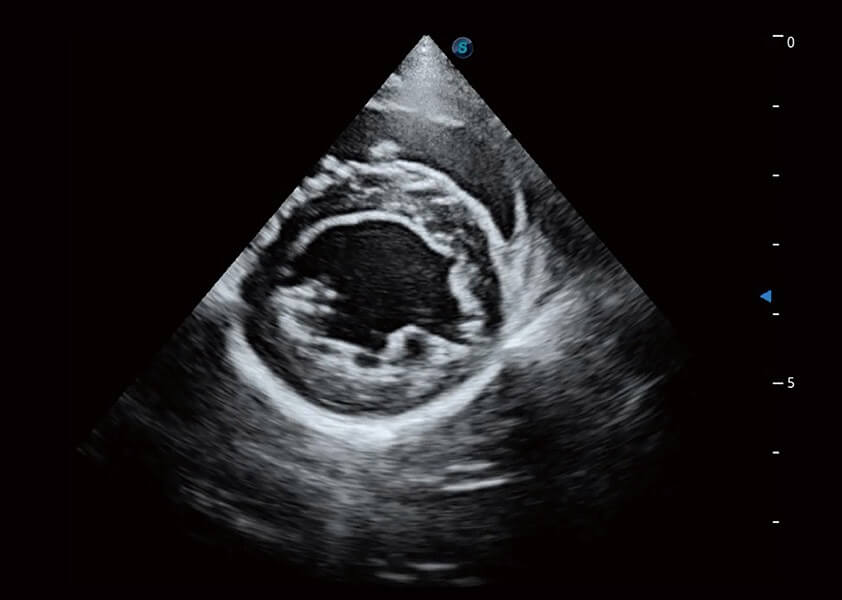

ProPet 60 作为一款高端台式动物超声设备,为动物医生的日常诊断提供了一系列贴合动物临床需求、解决临床实际问题的高级成像功能。凭借全系列高清探头,满足医生对腹部、心脏、生殖、浅表、肌骨等成像的所有需求,切实帮助您提升检查效率,提高诊断信心。

动物是人类最亲密的朋友和最值得信赖的伙伴。亚星官网也一直致力于探索动物专用的超声影像解决方案。 全新推出的ProPet系列,是亚星官网在动物超声影像智能化、专业化、精准化的一次跨越式革新。动物不能用言语来表述自己的不适,通过超声影像,ProPet系列搭建了动物医生与不同物种沟通的“桥梁”,为动物医生注入了“治愈之力”。